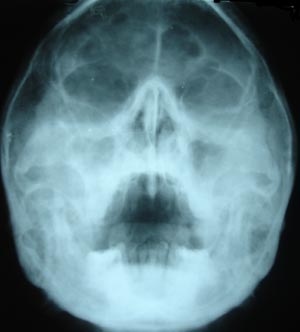

View Right Maxillary Sinusitis2

Right Maxillary Sinusitis 2

Water’s view, showing opacification of right maxillary sinus.